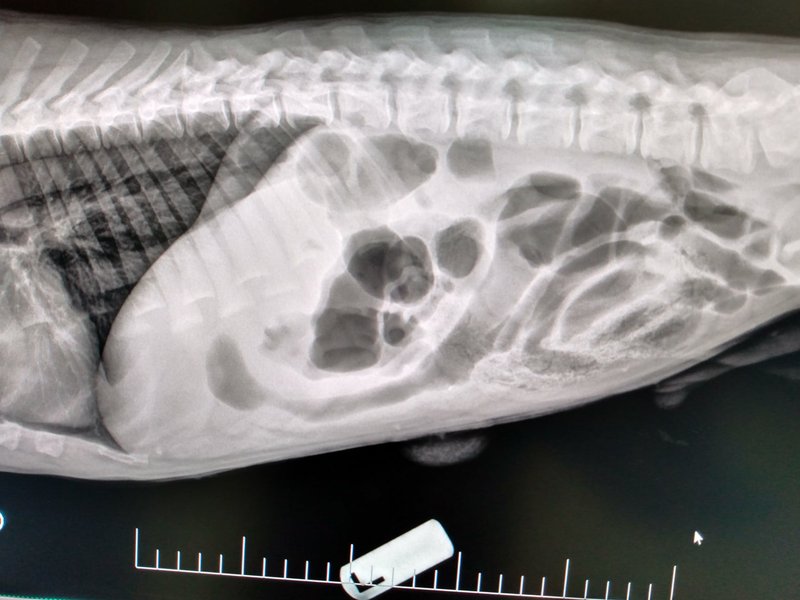

Ultrasound